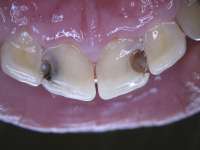

14736108869120.jpg (303Кб, 1824x1368)

Аноним 11/09/16 Вск 20:04:49  515332

>>515322